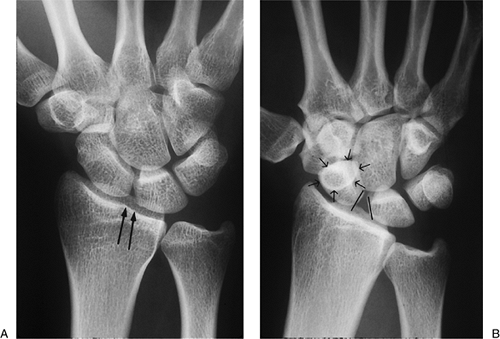

Figure 11.2-4 Comparison of x-ray findings in a normal wrist and in one with a scapholunate dissociation. A.

The normal appearance of the wrist in the AP view. Note the uniform spacing of the carpal bones, and more specifically, the parallel alignment of the articular interface between the proximal pole of the scaphoid and the lunate (parallel vertical arrows). B. A scapholunate dissociation showing a widened and nonparallel space between the scaphoid and lunate, a foreshortened scaphoid, and a positive “ring sign” (arrows in a circle). |